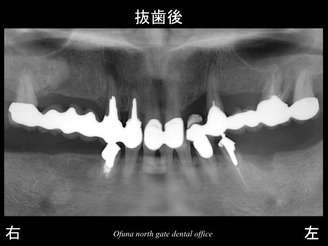

まず、歯根破折 を起こしている下顎左側の奥歯は、抜歯になりました。

下顎の 骨吸収の状態を線で書いたのが以下のレントゲンになります。

青線が骨吸収を起こす前の骨の位置です。

赤線は、現在の骨の位置です。

下顎左側の歯根破折 を起こしていた部位では、骨吸収が起こっています。

さらに わかりやすくするために、

骨吸収部位を赤色で表示します。

さらに骨吸収が大きいのが分かるかと思います。

以下がインプラント治療が終了した後のレントゲンです。